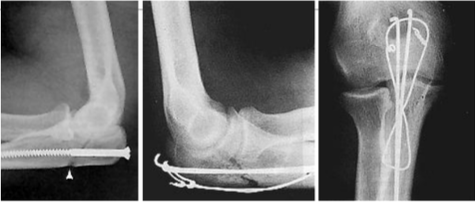

Tipo de fractura en la clasificacion de Mayo

1a (no desplazada, no conminutada)

2a (Desplazada estable, no conminutada)

3b (Desplazada inestable (por la luxacion) y conminutada)

Tratamiento de esta fractura

Conservador

Inmovilizar con yeso o ferula a 45-90°, inicio gradural de movilizacion a las 4 semanas

Obenque con clavillos de kirschner y alambre

Trtamiento de esta fractura

Fijacion con placa y tornillos (por multifragmentada)